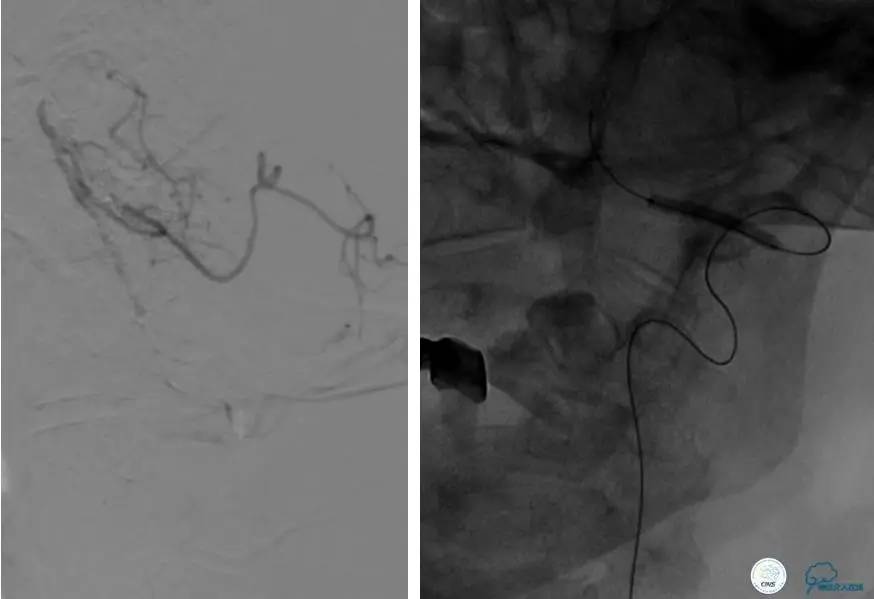

患者:49岁女性,脑梗死30天。

左侧颈内动脉末端闭塞,末端圆钝且有一定成角,开通难度较大,多次尝试导丝才成功穿过闭塞段。

开通效果很满意,术后症状明显恢复。

患者:反复发作右侧肢体无力、言语不清15天。

导丝很容易通过闭塞段。

顺利置入Wingspan支架,成功开通,手术顺利。